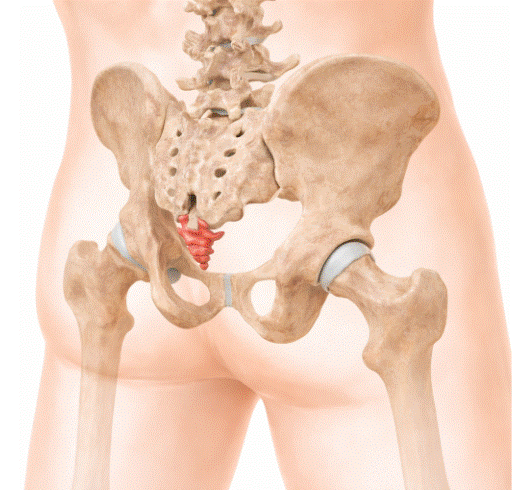

Fractura de estrés del metatarsiano: biomecánica y prevención

La fractura de estrés del metatarsiano es una lesión por sobrecarga frecuente en deportistas, militares y cualquier persona sometida a un aumento brusco de la carga de impacto sobre el pie, y su incidencia ha crecido de forma paralela al auge del running y los deportes de alta demanda física. A diferencia de las fracturas […]